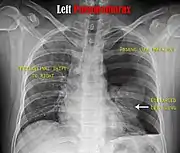

Chest X-ray

A plain chest radiograph, ideally with the X-ray beams being projected from the back (posteroanterior, or "PA"), and during maximal inspiration (holding one's breath), is the most appropriate first investigation.[30] It is not believed that routinely taking images during expiration would confer any benefit.[31] Still, they may be useful in the detection of a pneumothorax when clinical suspicion is high but yet an inspiratory radiograph appears normal.[32] Also, if the PA X-ray does not show a pneumothorax but there is a strong suspicion of one, lateral X-rays (with beams projecting from the side) may be performed, but this is not routine practice.[15][19]

Chest X-ray showing the features of pneumothorax on the left side of the person (right in image)

It is not unusual for the mediastinum (the structure between the lungs that contains the heart, great blood vessels, and large airways) to be shifted away from the affected lung due to the pressure differences. This is not equivalent to a tension pneumothorax, which is determined mainly by the constellation of symptoms, hypoxia, and shock.[13]

The size of the pneumothorax (i.e. the volume of air in the pleural space) can be determined with a reasonable degree of accuracy by measuring the distance between the chest wall and the lung. This is relevant to treatment, as smaller pneumothoraces may be managed differently. An air rim of 2 cm means that the pneumothorax occupies about 50% of the hemithorax.[15] British professional guidelines have traditionally stated that the measurement should be performed at the level of the hilum (where blood vessels and airways enter the lung) with 2 cm as the cutoff,[15] while American guidelines state that the measurement should be done at the apex (top) of the lung with 3 cm differentiating between a "small" and a "large" pneumothorax.[33] The latter method may overestimate the size of a pneumothorax if it is located mainly at the apex, which is a common occurrence.[15] The various methods correlate poorly but are the best easily available ways of estimating pneumothorax size.[15][19] CT scanning (see below) can provide a more accurate determination of the size of the pneumothorax, but its routine use in this setting is not recommended.[33]

Not all pneumothoraces are uniform; some only form a pocket of air in a particular place in the chest.[15] Small amounts of fluid may be noted on the chest X-ray (hydropneumothorax); this may be blood (hemopneumothorax).[13] In some cases, the only significant abnormality may be the "deep sulcus sign", in which the normally small space between the chest wall and the diaphragm appears enlarged due to the abnormal presence of fluid.[16]